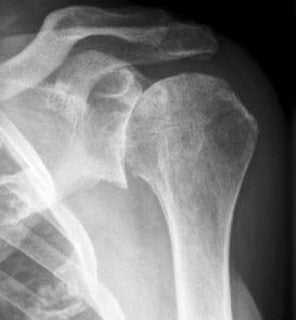

Рисунок плеча в ПОНР, вид спереди. Обзорные снимки во фронтальной проекции получают для визуализации плечевого сустава в косой аксиальной проекции с правильным направлением срезов параллельно телу плечевой кости. Рисунок плечевого сустава в ПОНР, вид сверху. Верхушка клювовидного отростка соответствует расположению переднего отдела суставной губы на 2:00 или 3:00 (в зависимости от положения пациента). Первая из 18 FS МР-артрограмм в ПОНР с направлением срезов сверху вниз. На этом срезе выше плечевого сустава видны клювовидный и акромиальный отростки. Рука пациента заведена за шею или за голову. Выполняется снимок во фронтальной проекции, а затем перпендикулярные ему срезы в косой аксиальной проекции параллельно телу плечевой кости. На этой томограме показано место прикрепления сухожилия подлопаточной мышцы к малому бугорку. Введенный в полость сустава контраст в норме может распространяться во влагалище сухожилия двуглавой мышцы. Визуализируется сухожилие длинной головки двуглавой мышцы, идущее вдоль проксимальной части межбугорковой борозды. На самых верхних срезах через плечевой сустав можно увидеть сухожилие длинной головки двуглавой мышцы. Также визуализируется место прикрепления сухожилия к суставной губе. В такой проекции относительно плохо различимы передне-задние (SLAP) разрывы в верхнем отделе суставной губы. При определенном положении руки сухожилие двуглавой мышцы может перекручиваться непосредственно проксимальнее места прикрепления к суставной губе. Перекрут сухожилия в некоторых случаях способен привести к SLAP-разрыву. На этом снимке частично визуализируется задневерхний отдел суставной губы. В ПОНР лучше всего визуализируется сектор суставной губы на 2:00-10:00. Около места прикрепления сухожилия подлопаточной мышцы можно увидеть среднюю суставно-плечевую связку. Суставно-плечевые связки могут образовывать складки на капсуле сустава. Передние пучки нижней суставно-плечевой связки растягиваются и огибают передний край головки плечевой кости. Сила растяжения передается на передний отдел суставной губы, увеличивая вероятность прохождения контраста и делая видимыми небольшие разрывы. На этом уровне может визуализироваться вдавление плечевой кости под суставную впадину в задневерхнем отделе. В бессимптомных случаях можно увидеть контраст между нижней поверхностью вращательной манжеты и суставной губой. Натяжение передних пучков нижней суставно-плечевой связки улучшает визуализацию разрывов суставной губы в положениях на 3:00-5:00, частично сращенных или заново покрытых синовиальной оболочкой. ПОНР позволяет визуализировать передне-нижний отдел суставной губы без феномена «магического угла», возникающего на артрограммах при стандартном отведении плеча. В ПОНР четко видны костно-хрящевые повреждения задневерхнего отдела головки плечевой кости (в данном случае отсутствуют). Разрывы суставной губы в передне-нижнем отделе проще обнаружить в ПОНР. Показана гладкая нижняя поверхность сухожилия подостной мышцы. В ПОНР имеется изгиб сухожилий надостной, подостной и малой круглой мышц, что позволяет контрастному веществу заполнять небольшие разрывы на нижней поверхности. ПОНР с успехом используется для выявления разрывов вращательной манжеты сделаминацией. Разрывы на нижней поверхности малой круглой мышцы в этом положении определяются лучше, по сравнению со стандартными МР-томограммами в положении отведения. Самый нижний срез, проходящий через суставную губу в положении 5:00-7:00. Точное расположение зависит от укладки пациента и конфигурации среза. Несмотря на то, что использование ПОНР позволяет улучшить визуализацию некоторых анатомических структур и поражений плечевого сустава, оно имеет и ряд ограничений. Основное из них состоит в том, что многие пациенты с болями в плече не могут переносить это положение. Кроме того, у специалиста, незнакомого с этой техникой, возникнут сложности с правильным расположением плечевой катушки и выбором конфигурации срезов.

• Выполняют обзорный снимок во фронтальной проекции

• Направление срезов вдоль тела плечевой кости:

о Визуализация вдоль длинной оси плечевой кости

о Получают снимки сустава в косой аксиальной проекции